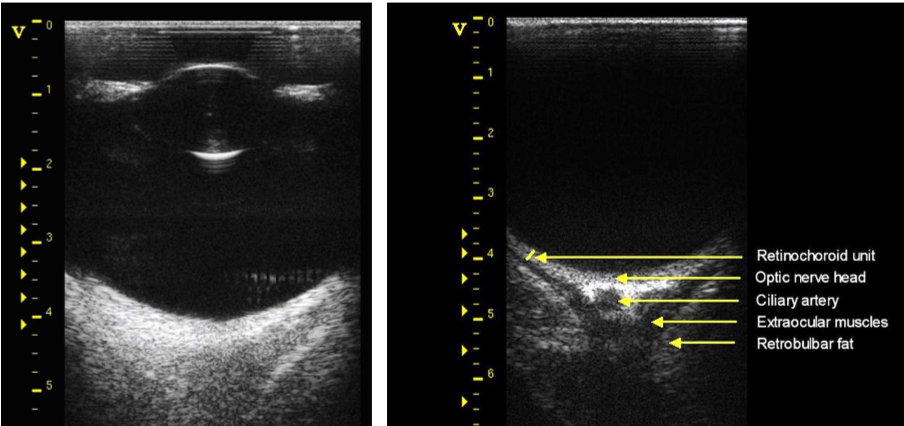

• Ultrasonography allows for vision into the back of the eye even if the cornea is cloudy/opaque

A) optic nerve

B) fat